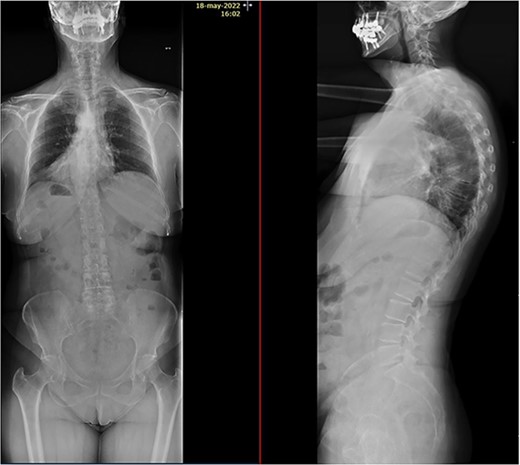

Imaging tests revealed a T7 pathologic fracture (Figs 1 and 2). First, X-ray-assisted percutaneous biopsy and kyphoplasty were inconclusive. Second, CT-assisted percutaneous biopsy and kyphoplasty revealed trabecular infiltration by hypercellular hyaline cartilage with cellular atypia, without relevant mitotic activity. Histological diagnosis of a Grade I chondrosarcoma was then established and the patient was directed to our clinic.

Alteration in the morphology and signal of the T7 vertebral body that presents a fracture with 30% loss of height and dorsal protrusion of posterior wall, with a left and epidural soft tissue component, the signal change extends to the left pedicle and part of the posterior arch. The right lateral margin of T8 vertebral body presents a hypointense signal on T1 and markedly hyperintense on STIR that indicates the presence of osseous edema. These findings suggest T7 pathological fracture and bone edema in the left T8 pedicle.

After PET scan, metastatic disease was discarded. Complete spine magnetic resonance and thoraco-abdominopelvic CT indicated the location on T7 vertebral body, with both end plates broken and causing a leakage to intervertebral disks. Moreover, an intensity change in the left pedicle of T8 was found, which could not be discarded as tumoral (Figs 2 and 3). Surgical resection been the only possible treatment, the patient was appointed to undergo total en bloc vertebrectomy of T7 and T8 and partial of caudal T6, following the technique described by Tomita et al. [1]

T7 pathological fracture with breakage of both superior and inferior end plates. Cement from the performed kyphoplasty is present, with leakage into the anterior paravertebral space.